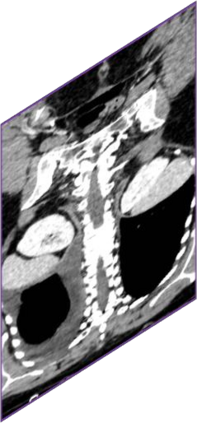

Due to the constraints of the imaging device and high cost in operation time, computer tomography (CT) scans are usually acquired with low intra-slice resolution. Improving the intra-slice resolution is beneficial to the disease diagnosis for both human experts and computer-aided systems. To this end, this paper builds a novel medical slice synthesis to increase the between-slice resolution. Considering that the ground-truth intermediate medical slices are always absent in clinical practice, we introduce the incremental cross-view mutual distillation strategy to accomplish this task in the self-supervised learning manner. Specifically, we model this problem from three different views: slice-wise interpolation from axial view and pixel-wise interpolation from coronal and sagittal views. Under this circumstance, the models learned from different views can distill valuable knowledge to guide the learning processes of each other. We can repeat this process to make the models synthesize intermediate slice data with increasing inter-slice resolution. To demonstrate the effectiveness of the proposed approach, we conduct comprehensive experiments on a large-scale CT dataset. Quantitative and qualitative comparison results show that our method outperforms state-of-the-art algorithms by clear margins.